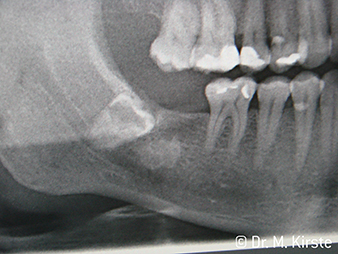

Exemple patient W&H

Ill. 7 :

… est soigneusement extraite à l’aide du nouveau

contre-angle.